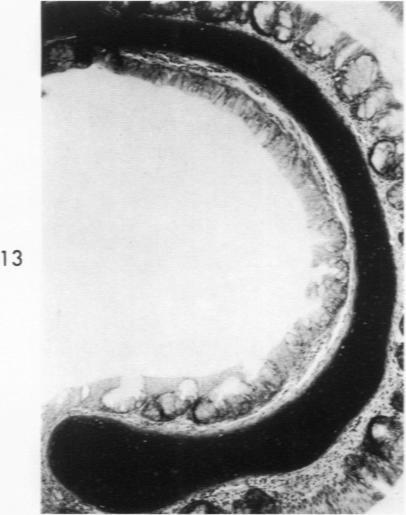

Acute Newcastle disease virus infection following intranasal inoculation of chicks with a mesogenic strain of the virus produced a localized infection of the middle turbinate which was histologically demonstrable 18 hours after inoculation. There was destruction of mucous cells of individual acini in the under surface of the middle turbinate, and the infection rapidly spread to ciliated and goblet cells and to neighboring acini. By day 2 there was simultaneous remodeling of the mucosa, continued destruction and inflammatory infiltration and frequent loss of cartilage basophilia. By day 3 polymorphonuclear cells almost disappeared, epithelial mitoses commenced, and lymphocyte infiltration intensified; the plasma cells normally present along the lateral nasal gland ducts were often destroyed, very occasionally the glands themselves were destroyed. By days 5 and 6 inflammation greatly decreased, and by day 8 the mucociliated epithelium was essentially normal. The infection is sequentially comparable to acute mild rhinitis of man.

用新城疫病毒的中等毒力株经鼻腔接种雏鸡后,会引发急性感染,在接种后18小时可通过组织学方法证实中鼻甲出现局部感染。中鼻甲下表面单个腺泡的黏液细胞遭到破坏,感染迅速蔓延至纤毛细胞、杯状细胞及相邻腺泡。到第2天,黏膜同时发生重塑,破坏和炎性浸润持续存在,软骨嗜碱性常常丧失。到第3天,多形核细胞几乎消失,上皮细胞开始有丝分裂,淋巴细胞浸润加剧;沿鼻外侧腺管通常存在的浆细胞常被破坏,腺管本身偶尔也会被破坏。到第5天和第6天,炎症大为减轻,到第8天,黏液纤毛上皮基本恢复正常。这种感染过程与人的急性轻度鼻炎有相似之处。